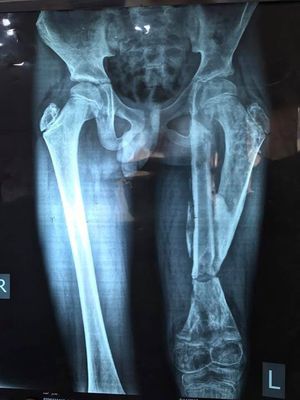

Middle segment of femur dislocated from proximal end and joined the acetabulum, bone setter displaced after, failed alignment

Malunion

It's the overgrowth of the the distal segment as a sequester . The patient is also too young and he visited the hospital after 6 months